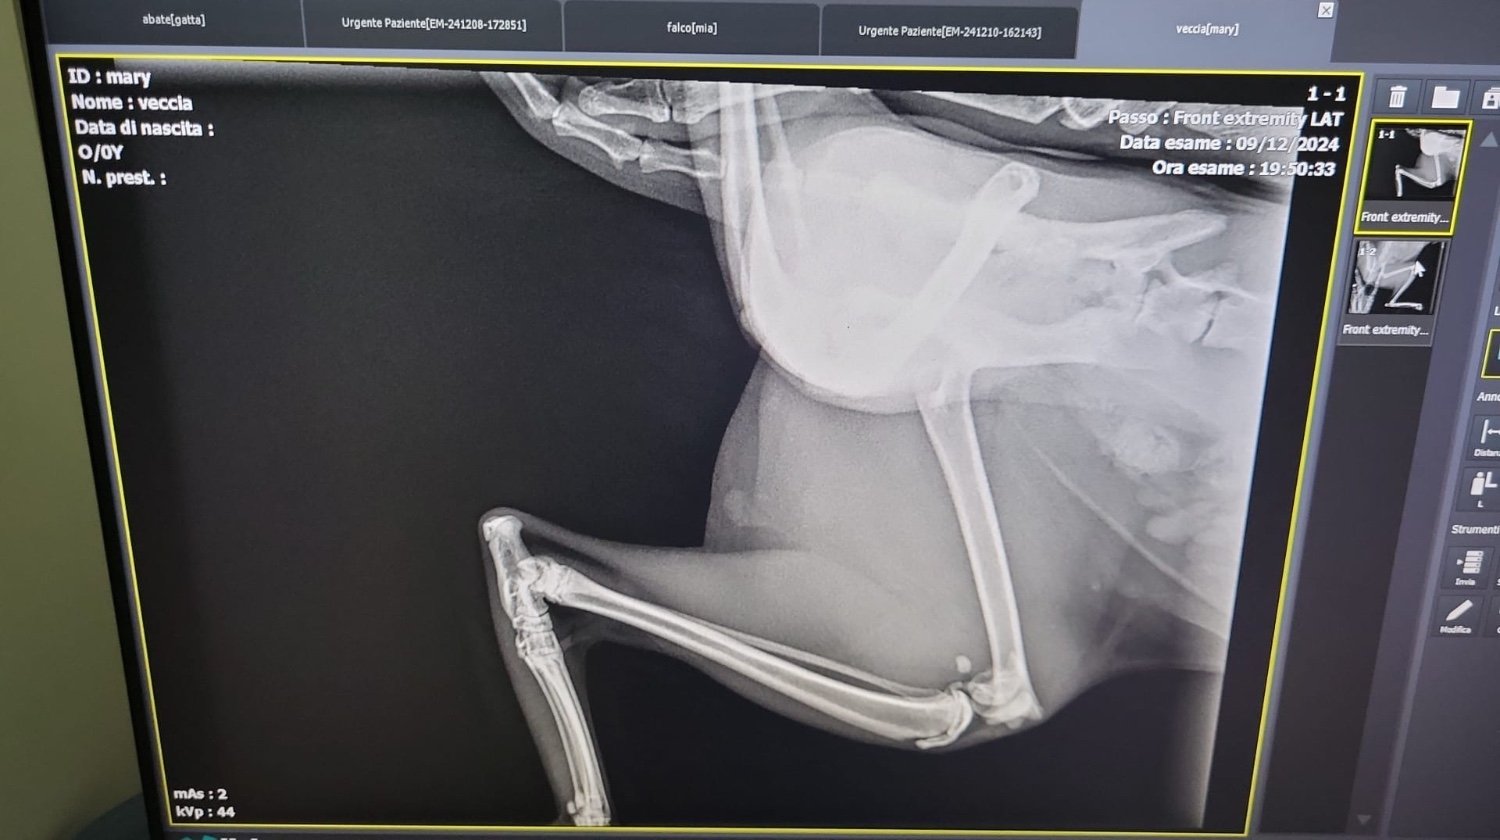

Mõned päevad tagasi leidsime Marie, väga armsa, alla aastase kassipoisi, kes oli abi otsides varjupaika läinud. Ta päästes saime aru, et tal on käpp katki. Viisime ta kohe loomaarsti juurde ja saime teada, et käpa päästmiseks vajalik operatsioon on üsna kallis.